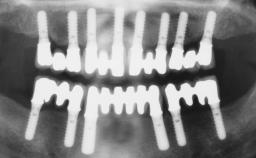

Conventional Loading of Eight Implants in the Maxilla and Final Restoration with a Full-Arch Gold-Ceramic FDP

A 35-year-old Caucasian female presenting with advanced periodontal disease involving both the maxillary and the mandibular dentition was referred for evaluation. The patient, a non-smoker in good general health, requested treatment for recurrent periodontal abscesses, tooth mobility, and discomfort during chewing, as well as restoration of her missing teeth with a fixed prosthesis to improve mastication and esthetics. All residual maxillary teeth exhibited plaque deposits, deep pockets, bleeding on probing, and class III mobility and were evaluated as hopeless. All residual mandibular teeth except tooth 37 could be maintained after periodontal therapy.

# of Implants | 8 |

Type of Implants | One-Piece |